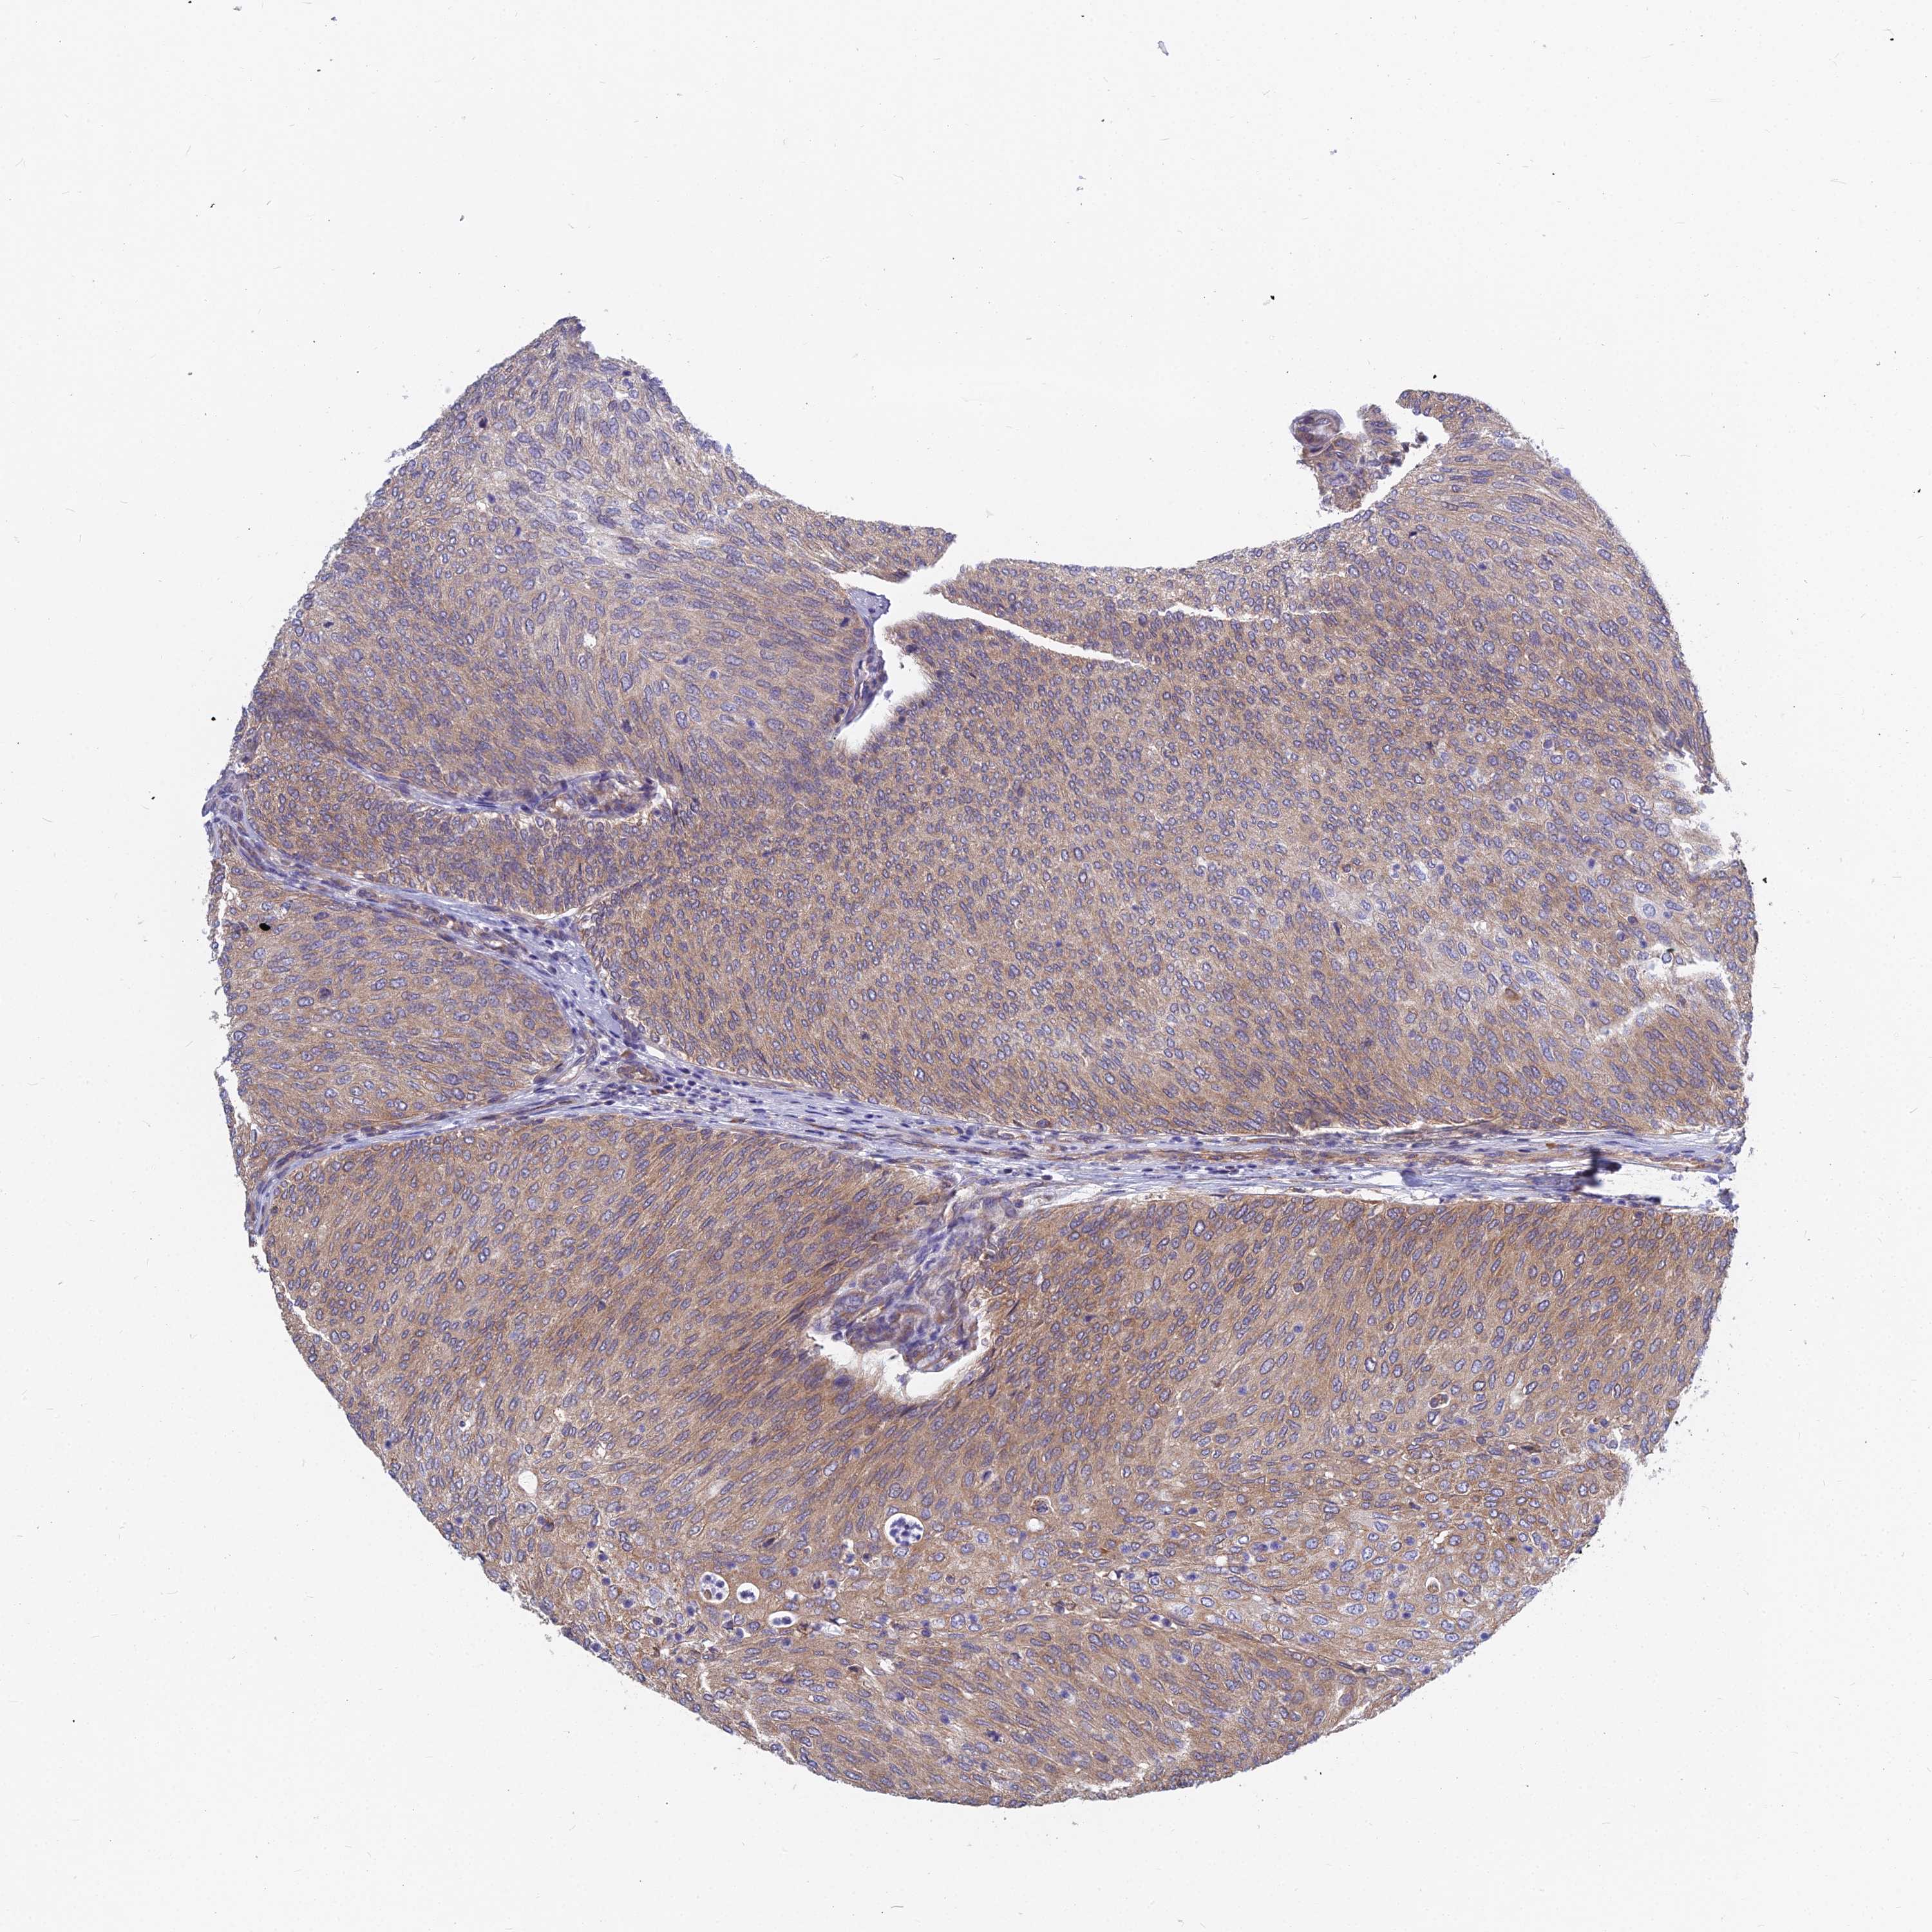

UROTHELIAL CANCER - Protein expressioni

A mouse-over function shows sample information and annotation data. Click on an image to view it in a full screen mode. Samples can be filtered based on level of antibody staining by selecting one or several of the following categories: high, medium, low and not detected. The assay and annotation is described here.

Note that samples used for immunohistochemistry by the Human Protein Atlas do not correspond to samples in the TCGA dataset.

Antibody stainingi

Antibody staining in the annotated cell types in the current human tissue is reported as not detected, low, medium, or high, based on conventional immunohistochemistry profiling in selected tissues. This score is based on the combination of the staining intensity and fraction of stained cells.

Each image is clickable and will lead to virtual microscopy that enables deeper exploration of all samples and also displays staining intensity scores, fraction scores and subcellular localization as well as patient and tissue information for each sample.

Antibody HPA045018

Staining

High

Medium

Low

Not detected

Intensity

Strong

Moderate

Weak

Negative

Quantity

>75%

75%-25%

<25%

None

Location

Nuclear

Cytoplasmic/membranous

Cytoplasmic/membranous,nuclear

Urothelial carcinoma, Low grade